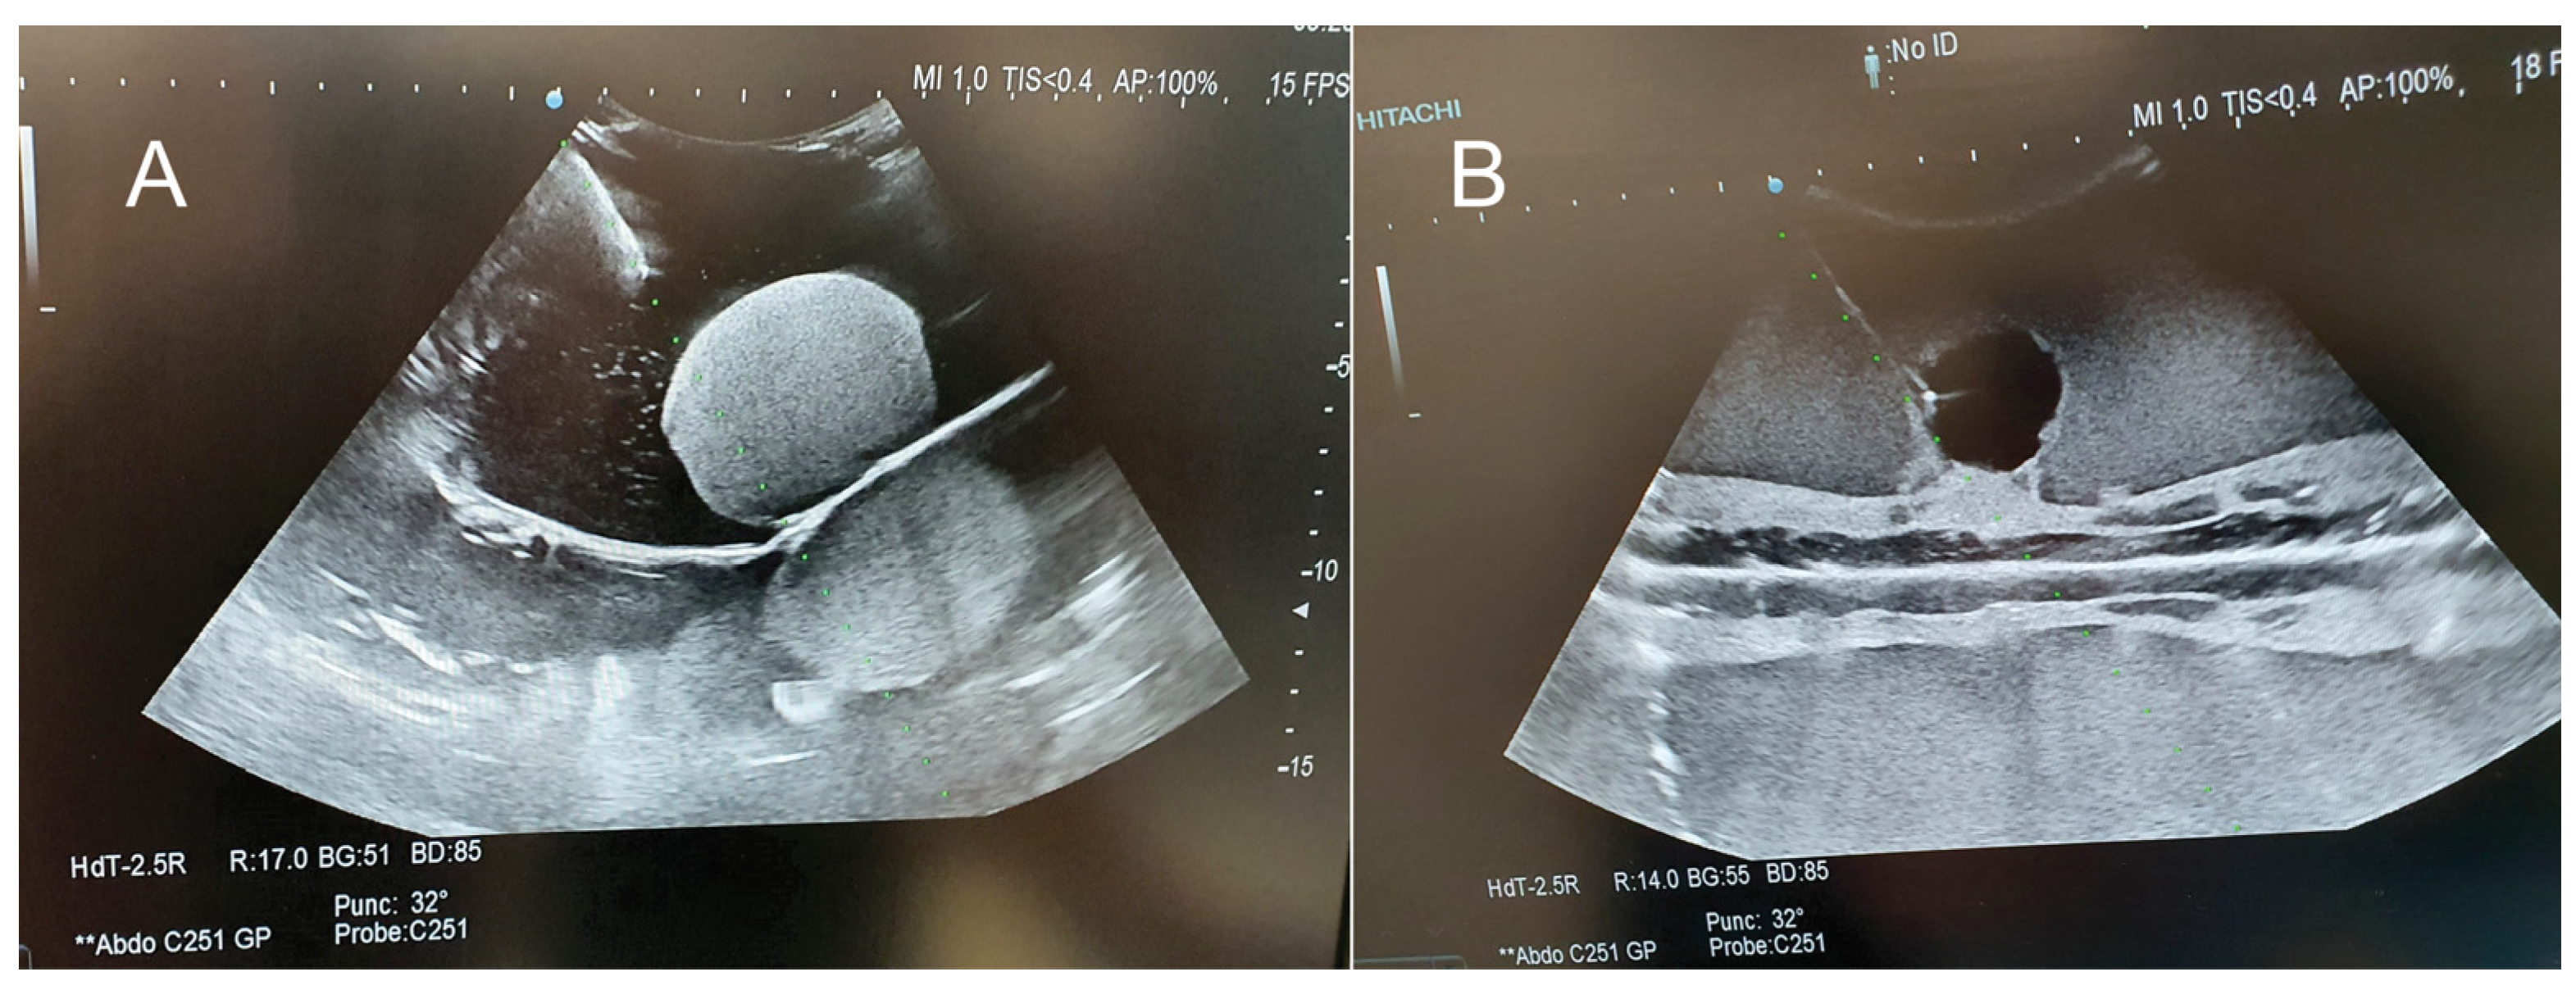

2. Materials and Methods

- Criteria 1: hardness—how hard/soft is the model when handling;

- Criteria 4: optimal characteristics for ultrasound—how optimal/not optimal is the model for ultrasound examination;

- Criteria 7: optimal for multiple punctures—how well/not well does the model behave for multiple puncture;

- Criteria 8: puncture resistance—how easy/difficult is to puncture the model;

- Criteria 9: optimal for training in ultrasound-guided procedures—how optimal/not optimal is the model for ultrasound-guided procedures.

3. Results

4. Discussion